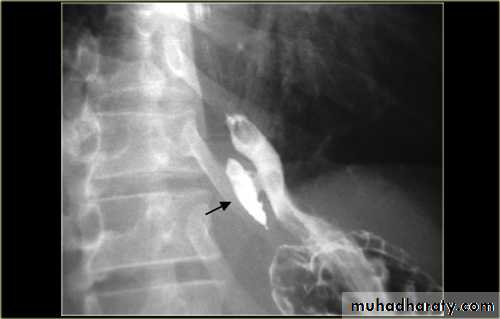

Diverticulum

Types Causes Specific TypeUlcer